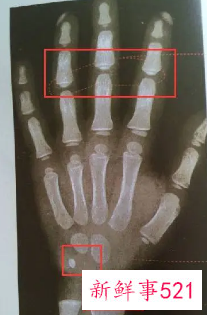

比较简单的方法就是去拍一个X光,借助于骨骼在X光摄像中的特定图像来确定。通常要拍摄人左手手腕部的X光片,医生通过X光片观察左手掌指骨、腕骨及桡尺骨下端的骨化中心的发育程度,来解读确定骨龄。

骨龄鉴定是指人的生长发育可用两个“年龄”来表示,即生活年龄(日历年龄)和生物年龄(骨龄)。骨龄是骨骼年龄的简称,借助于骨骼在X光摄像中的特定图像来确定。在了解人的骨龄情况时,通常要拍摄人左手手腕部的X光片,医生通过X光片观察左手掌指骨、腕骨及桡尺骨下端的骨化中心的发育程度,来确定骨龄。